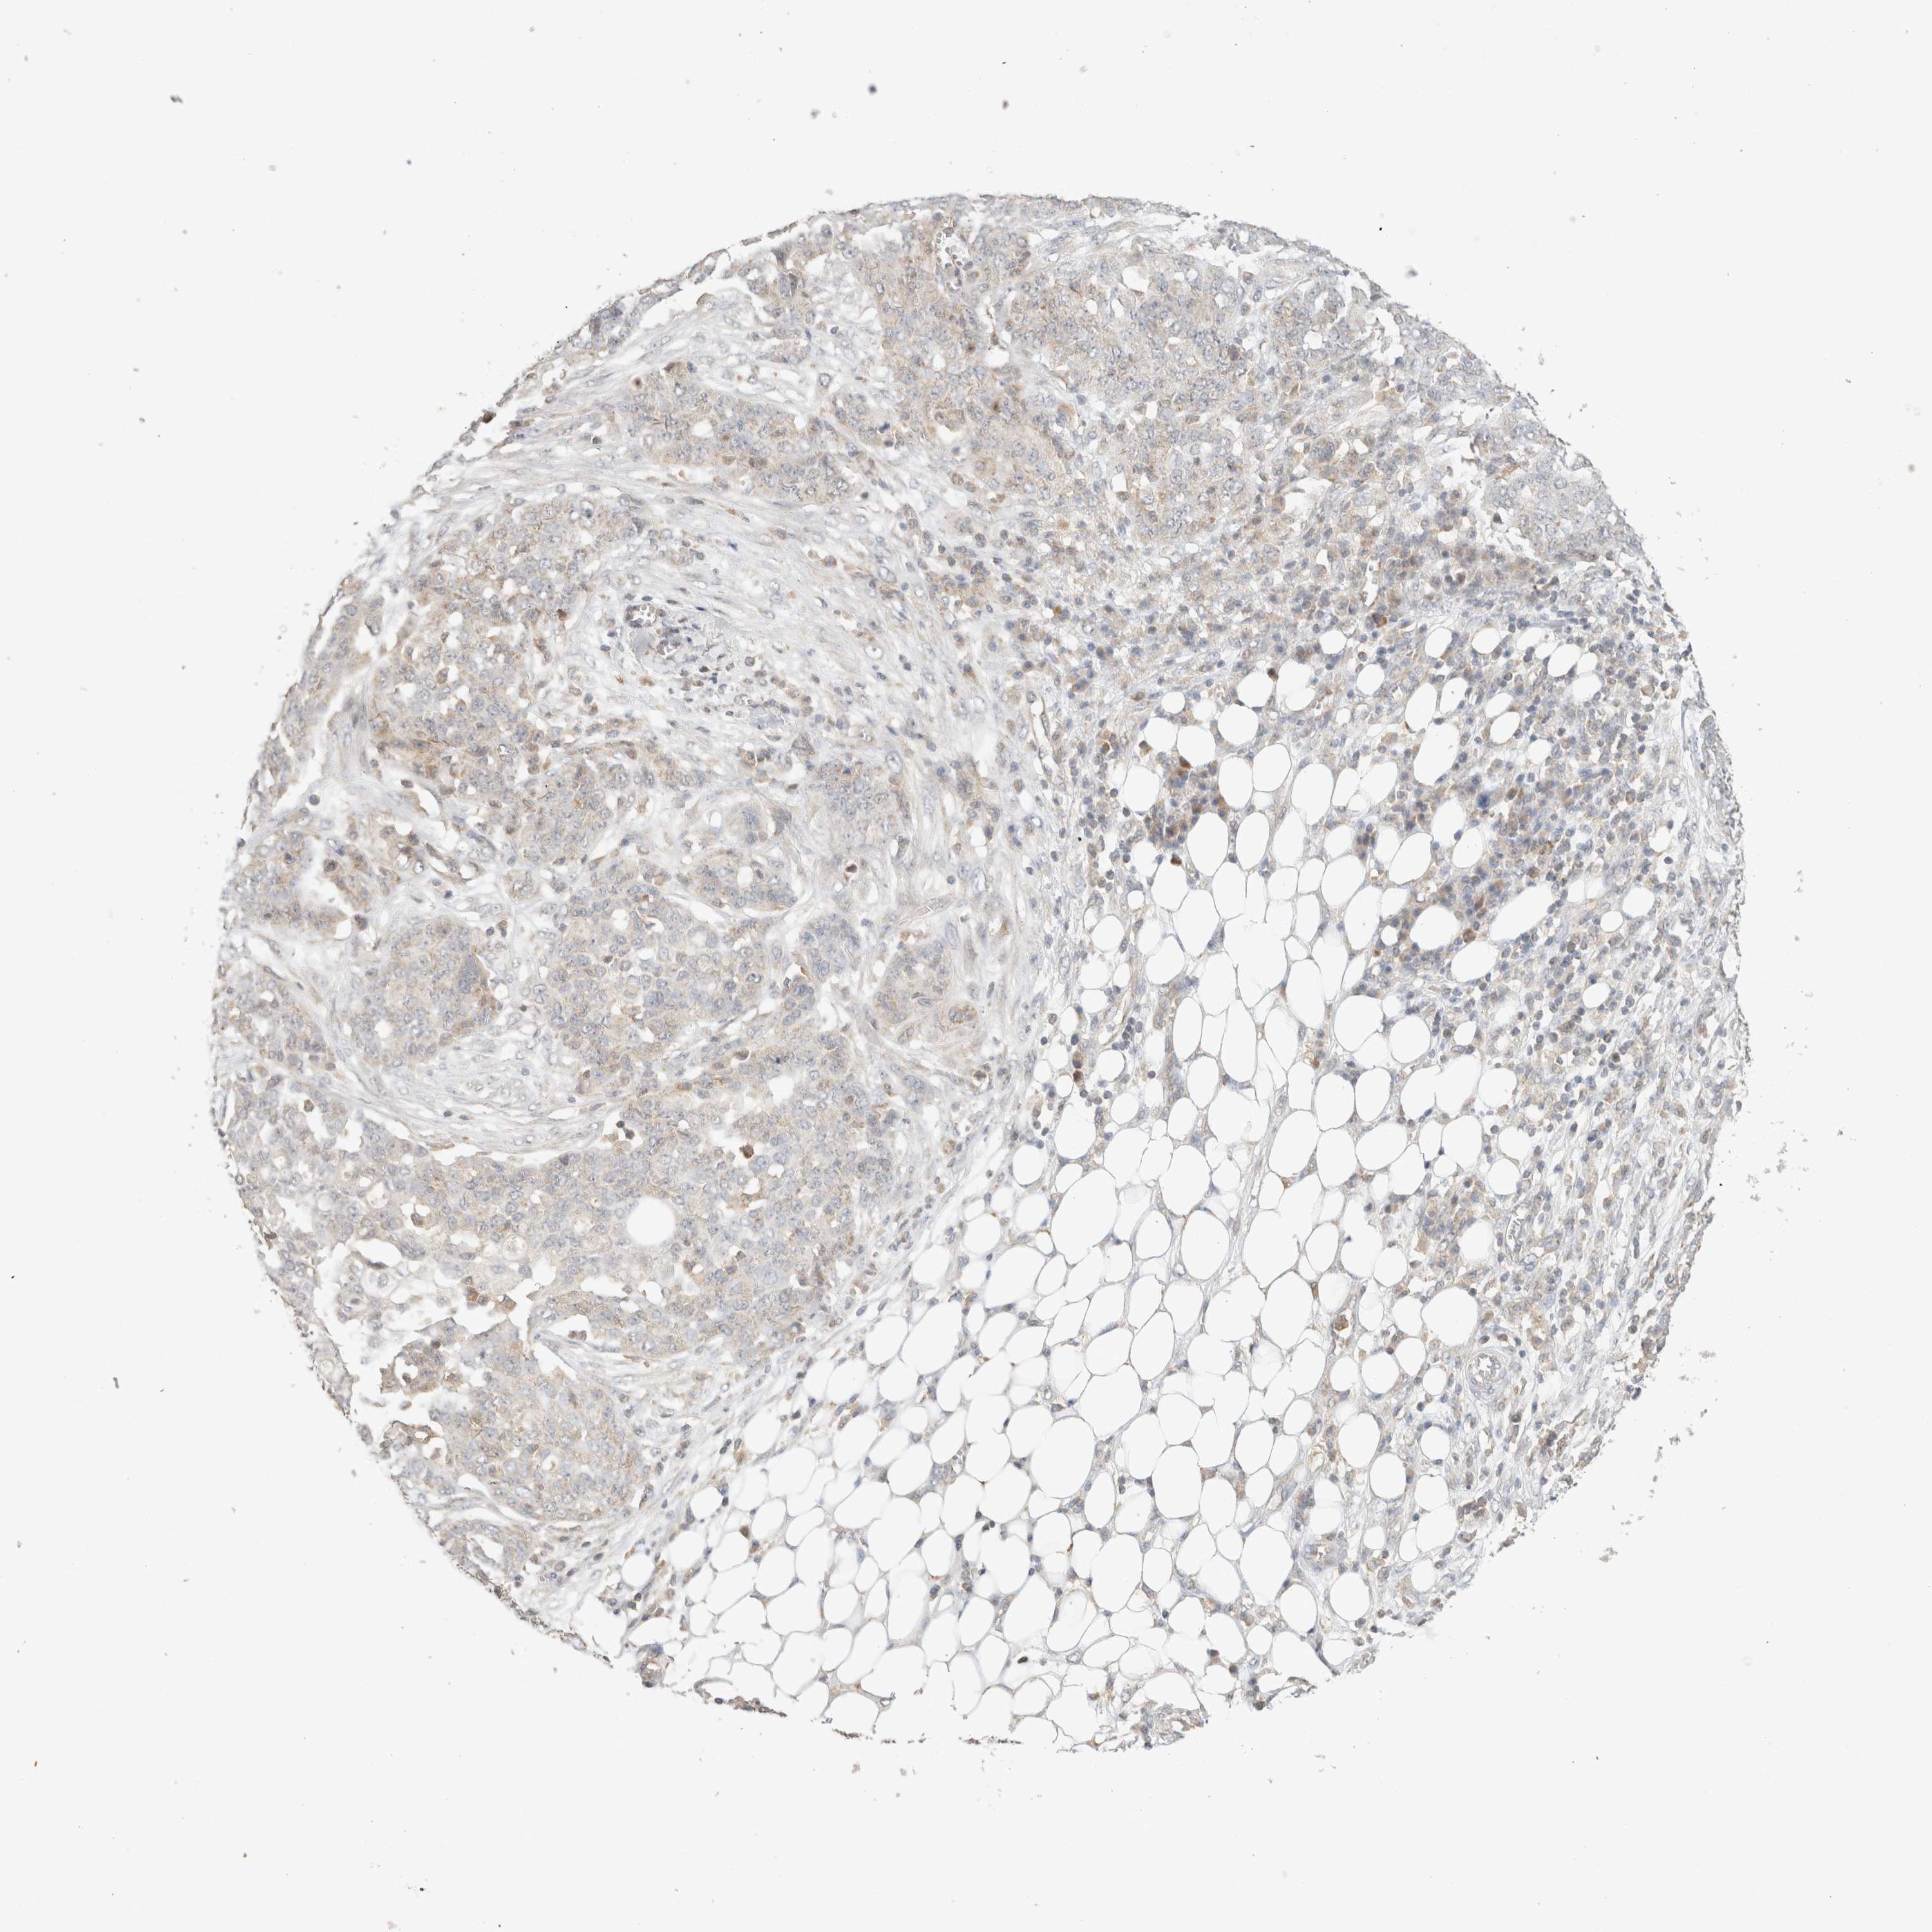

OVARIAN CANCER - Protein expressioni

A mouse-over function shows sample information and annotation data. Click on an image to view it in a full screen mode. Samples can be filtered based on level of antibody staining by selecting one or several of the following categories: high, medium, low and not detected. The assay and annotation is described here.

Note that samples used for immunohistochemistry by the Human Protein Atlas do not correspond to samples in the TCGA dataset.

Antibody stainingi

Antibody staining in the annotated cell types in the current human tissue is reported as not detected, low, medium, or high, based on conventional immunohistochemistry profiling in selected tissues. This score is based on the combination of the staining intensity and fraction of stained cells.

Each image is clickable and will lead to virtual microscopy that enables deeper exploration of all samples and also displays staining intensity scores, fraction scores and subcellular localization as well as patient and tissue information for each sample.

Antibody HPA022534

Antibody HPA023031

Antibody HPA023292

Cystadenocarcinoma, serous, NOS